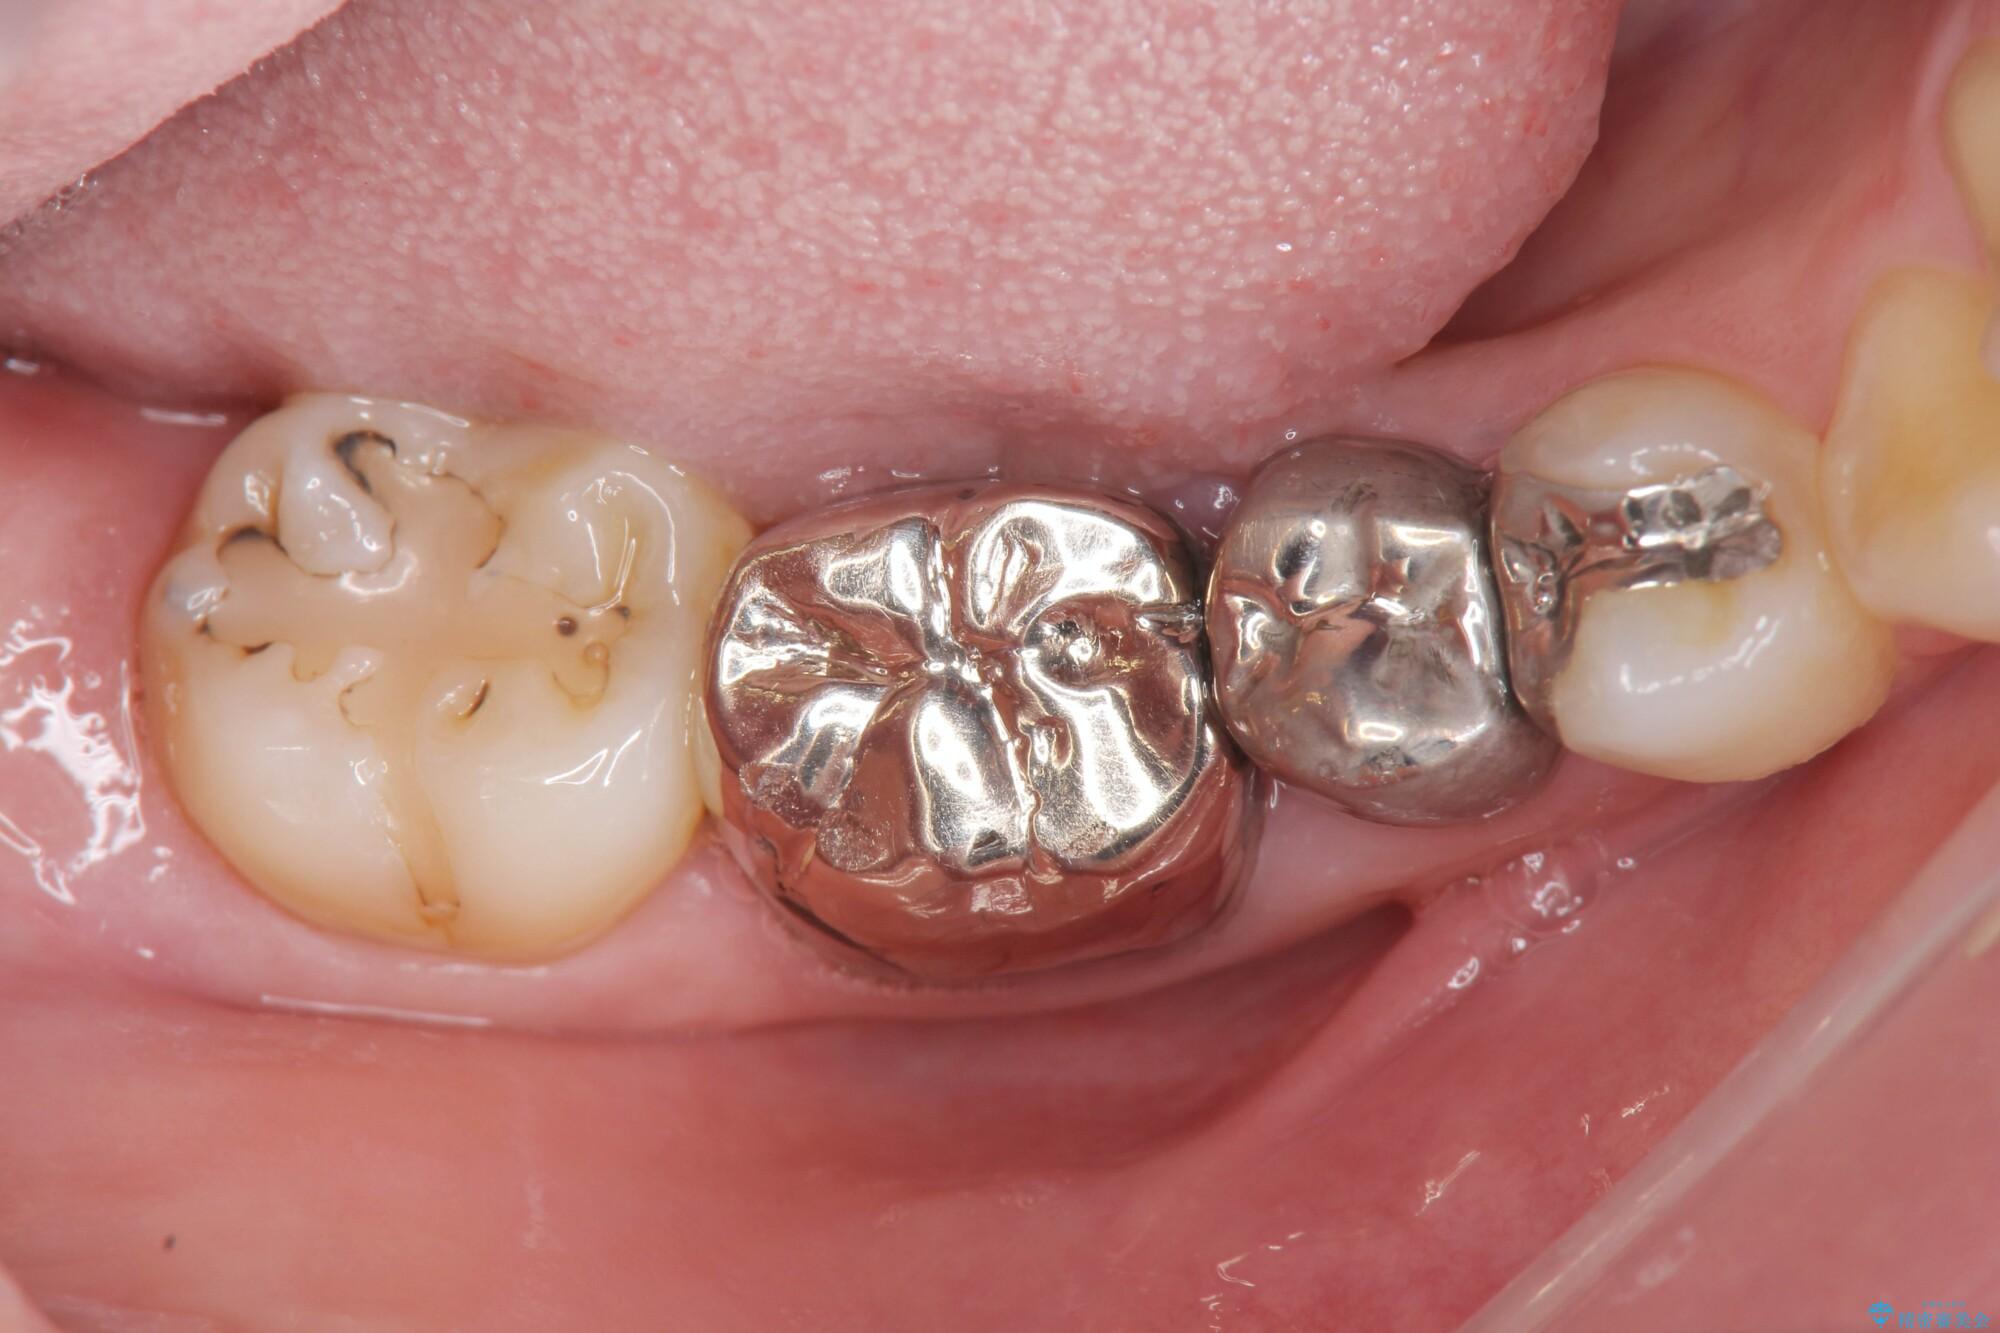

銀歯周辺の歯ぐきが疼くとご相談にいらっしゃった患者様です。

装着されていた清掃性の悪い銀歯を外すと、銀歯の下で歯ぐきよりも深い虫歯が再発していました。